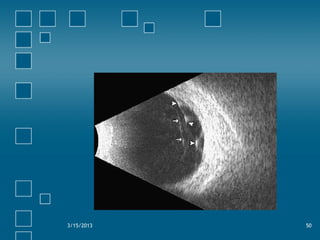

• Tractional R/D:

− Traction membranes are seen

− R/D usually doesn’t extend to ora serrata

− Lower mobility in contrast to Rheg. R/D